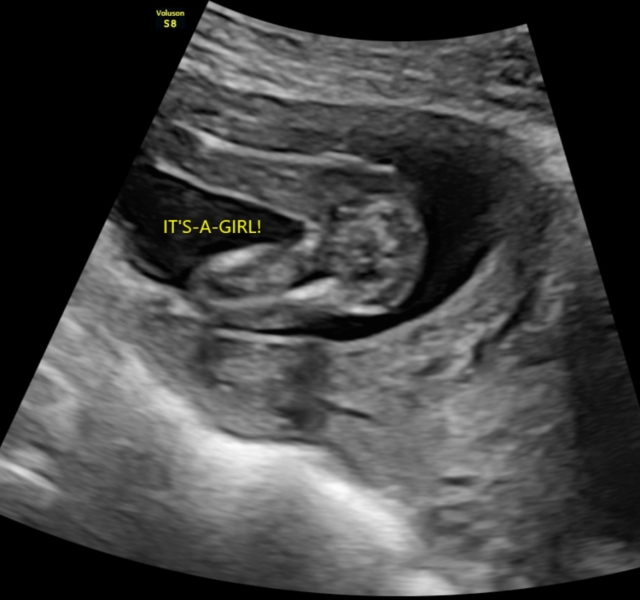

Had a private gender scan at 15+5 weeks and was told it was a girl but i’m unsure after looking at the scan images.

Private Gender Scan Right?